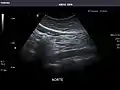

Kidneys: Right and left kidneys measure 11.5 cm and 12 cm in length respectively. No hydronephrosis. Small left lower pole kidney cyst.

Right kidney